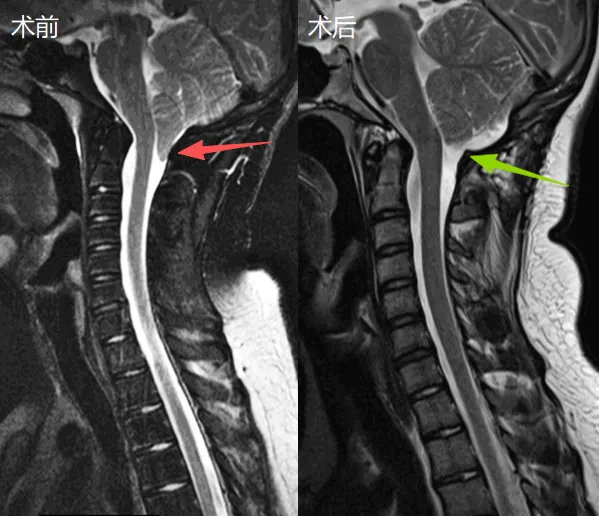

在得知自己患有预后良好的Chiari I型畸形,且手术后有很大机会重返橄榄球运动后,约翰最终决定接受手术治疗。在Rutka(鲁特卡)教授主刀下,手术过程十分顺利。术后约翰未再出现头痛发作,不久后便重新投入日常训练,并在后续橄榄球比赛中取得优异成绩!